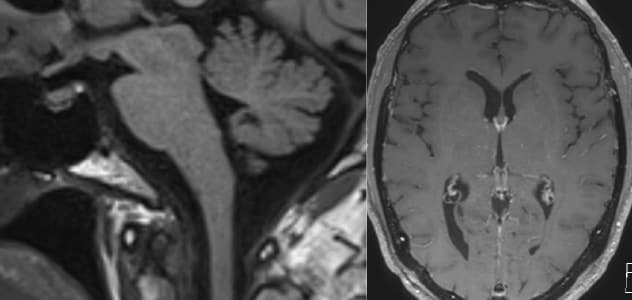

يُظهر التصوير بالرنين المغناطيسي السابق للجراحة لأحد المشاركين في سلسلة حالات مايو كلينك مؤشرات على ضعف الدماغ مع تسطيح الجسر، وقصر المسافة بين الأجسام الحلمية والجسر وانمحاء الكيسات فوق السرج، بالإضافة إلى تعزيز سُمك غشاء الجافية.

يوضح التصوير بالرنين المغناطيسي اللاحق للجراحة الشفاء من حالة ضعف الدماغ وتعزيز السحايا.